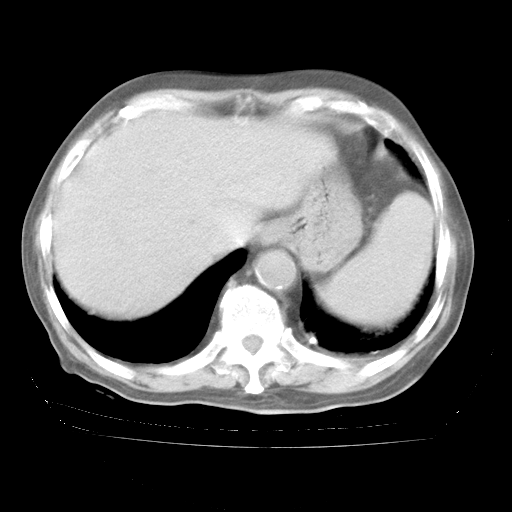

4月28日肺部CT——再次出现类似去年5月9日——透光度降低,“间质性”改变。

4月28日肺部CT——再次出现类似去年5月9日——磨玻璃样、间有“粟粒样”改变。

4月28日肺部CT